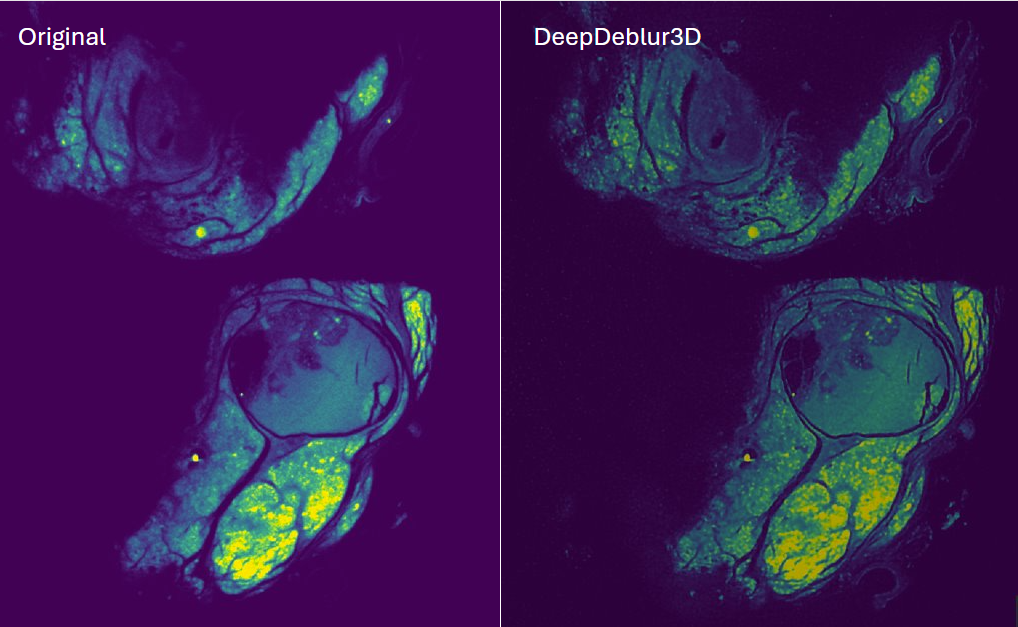

A 3D U-Net for simultaneous denoising and sharpening of micro-CT scans, trained on 467 heterogeneous volumes across multiple scanners and sample types.